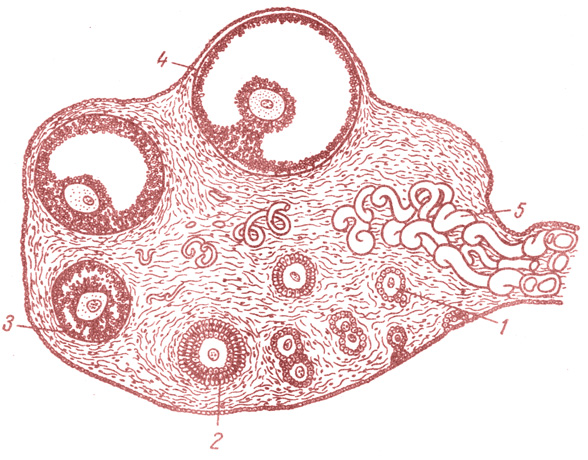

Созревание фолликула в яичнике: этапы и процессы